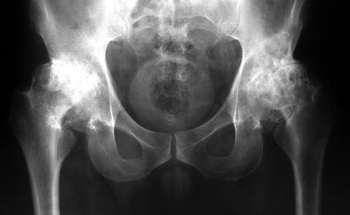

În urmă cu doi ani, am început să am dureri ușoare la genunchi și la șold. Durerea nu era gravă, nu i-am dat prea multă atenție... După cum se pare, bolile articulare sunt foarte grave și trebuie de luptat cu ele imediat, și a nu amăna cum am făcut-o eu! Într-o zi am simțit o durere ascuțită, dar nu foarte puternică, în genunchi, iar șoldul începea să mă doară într-adevăr tare . Am cumpărat câteva remedii și unguente și am început să le folosesc. Am răbdat durerea timp de aproximativ 1 săptămână, starea mea a început să se înrăutățească, durerea a devenit insuportabilă, a început o durere puternică în articulația șoldului, am luat decizia sa apelez la un specialist pentru prima dată. Nu a fost ieftină consultarea, iar specialistul meu s-a uitat la rezultate și a spus:

"De ce ai ignorat simptomele înainte? Aveți artroză! Dacă vreți să evitați să ajungeți într-un scaun cu rotile, trebuie să vă operați la șold și la genunchi!"

Pe scurt, am fost șocată!!! Am intrat în panică, nu aveam bani pentru operație și eram total nepregătită pentru ea! Costul operației a fost uriaș.... Și nu eram sigură că aș putea supraviețui după o astfel de operație la bătrânețe. M-am hotărât sa nu fac operația și l-am rugat să-mi prescrie un curs de recuperare.

Artroplastia articulară este foarte costisitoare și este o operație foarte serioasă.